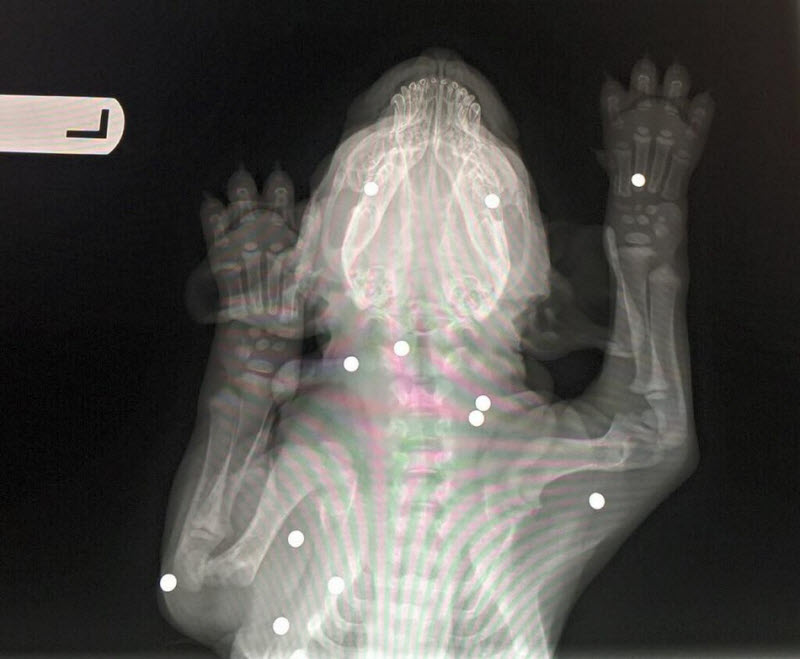

エアガンを18回撃ち込まれた子犬が発見される

gif_animation アメリカより、エアガンの弾を18回も撃ち込まれた生後6週間の子犬。警察による捜査の結果、14歳と17歳の少年2人が捕まり、動物虐待の容疑で起訴されたそう。ちなみに子犬は驚異的な回復力を見せており、命に別状はないとの事。[6]images